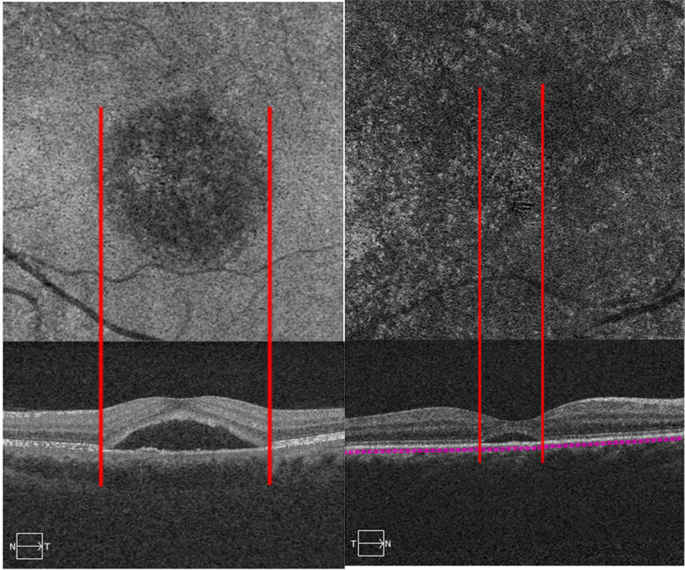

All type B abnormality collocated with SRF on structural OCT. Patients with type B abnormality exhibited a greater mean maximum SRF thickness than patients without type B abnormalities (538.0 ± 230.8 µm versus 242.8 ± 180.1 µm; P < 0.01) (Fig. 4). Type B abnormality presented in 36 eyes with acute CSC and 13 eyes with chronic CSC (54.5% vs. 19.7%, respectively; P = 0.001).

En face choriocapillaris optical coherence tomography angiography (OCTA) images and the B-scan of the same central serous chorioretinopathy (CSC) patients. Patient with type B (left panel) showed the extent of subretinal fluid (SRF) on B-scan corresponding with the area of type B abnormalities on OCTA. Patients with a thinner SRF did not exhibit the corresponding halo on OCTA (right panel).